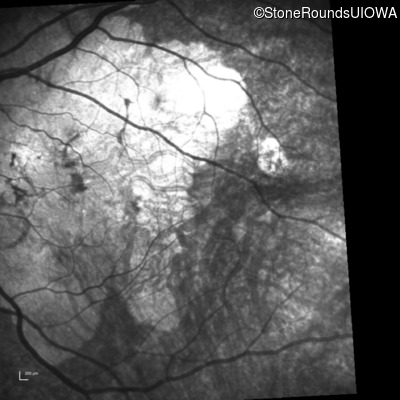

Infrared Fundus Photograph - Right - 20/100 +1

Exemplar